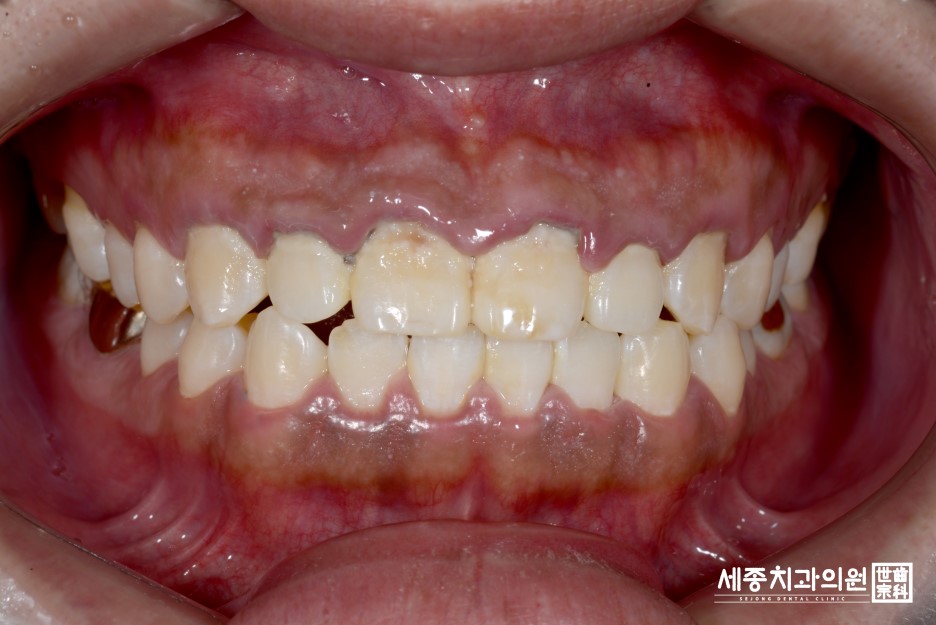

다행히 충치는 없었지만, 음주와 흡연으로 인한 치아 착색이 심했었고,

그동안 한 번도 스케일링을 받지 않아서 치석이 잇몸 속에도 쌓여서 잇몸이 부어서

스케일링과 함께 치주 스케일링을 받아야 한다는 진단이 내려졌습니다~

정홍민 환자분8.jpg

사진상으로 치아 위쪽 잇몸이 부어오르신 거 보이시죠?!

제때 스케일링을 받지 않은 것이 원인이라고 합니다.

정홍민 환자분 스케일링 전, 후 얼마나 달려졌는지 한번 볼까요?!

정홍민 환자분18.JPG

부어있던 잇몸도 많이 가라앉고, 치석제거로 인해 치아와 잇몸의 경계가 깔끔해지고

한눈에도 좋아진 모습이죠?!